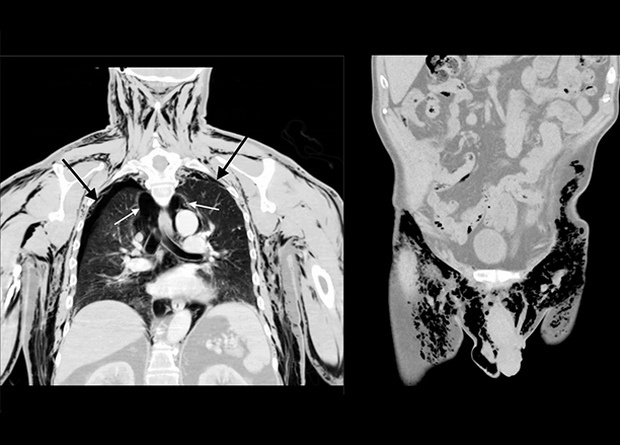

Американские врачи отчитались о необычном клиническом случае, при котором пожилой пациент поступил в кабинет неотложной помощи с жалобами на одышку, отек лица и свистящий звук из паховой области. Причиной стало поступление воздуха по неустановленному механизму под кожу, в плевральную полость, средостение и мошонку, из которой он выходил наружу через открытую рану после неудачной операции. Сообщение опубликовано в American Journal of Case Reports.

При определенных условиях воздух может попадать в несвойственные для него отделы организма, такие как мягкие ткани (это называется эмфиземой с указанием пораженной области) или серозные полости (такие состояния именуют приставкой «пневмо-», например, пневмоторакс в плевральной полости, пневмоперитонеум — в брюшной, пневмомедиастинум — в средостении, пневмоскротум — в мошонке). Причиной этого могут стать травмы, хирургические вмешательства, разрывы полых органов (таких как легкое или кишка), реже — газовая гангрена или попадание воздуха при самостоятельных инъекциях. При пальпации тканевой эмфиземы можно услышать крепитацию (похрустывание), а в присутствии открытой раны — тихий свист. Также эти звуки могут появляться при произвольных или дыхательных движениях.